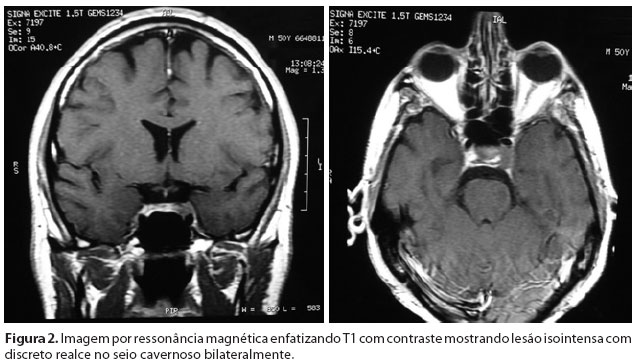

Aos exames laboratoriais, verificou-se leucopenia (2.500 leucócitos,com 46% de neutrófilos e 42% de linfócitos), acometimento renal (creatinina: 4,0 mg/dl e uréia: 69 mg/dl) e hepático (TGP: 130 U/L, fosfatase alcalina: 376 UI e gama GT: 452 UI) e hipoproteinemia (proteínas totais: 4,8 g/dl, albumina: 2,1 g/dl e globulinas 2,7 g/dl). A imagem por ressonância magnética (IRM) enfatizando T1 evidenciou lesão isointensa, com discreto realce após administração de gadolínio localizada em ambos os seios cavernosos, mais evidente à esquerda (Figura 2). Devido à suspeita de lesão neoplásica, foi realizado estudo histopatológico da lesão axilar que evidenciou hiperplasia linfóide atípica e a biópsia da medula óssea evidenciou infiltração de células linfóides fortemente sugestiva de linfoma não-Hodgkin. Algumas semanas após o diagnóstico, o paciente desenvolveu falência renal e hepática.